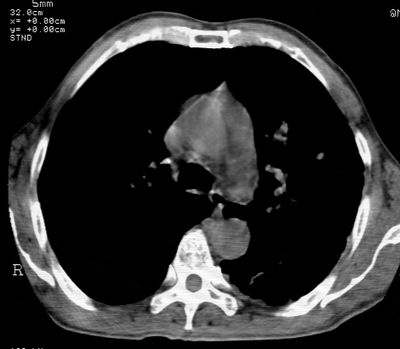

标题: CT24000:M65,胸痛,胸闷月余,既往慢支,肺气肿,肺心病 [打印本页]

标题: CT24000:M65,胸痛,胸闷月余,既往慢支,肺气肿,肺心病

左肺门肿块,相应支气管闭塞,左肺上叶、舌叶大片及散在高密度影,部分呈不张改变,两肺纹粗乱,左侧胸腔积液。考虑左侧中央型肺癌伴阻塞性改变。

左肺门见巨大软组织肿块影,直径约--,境界清,左上肺叶支气管变窄,左上肺舌叶见大片状密实影,余肺纹理增多、紊乱、纤细、部分网格状,两肺透亮度增高,纵隔内见增大多发淋巴结影,心影略左偏,左侧少量胸腔积液。

左侧中央型肺癌伴左上肺舌叶不张、纵隔淋巴结转移,左侧少量胸腔积液。